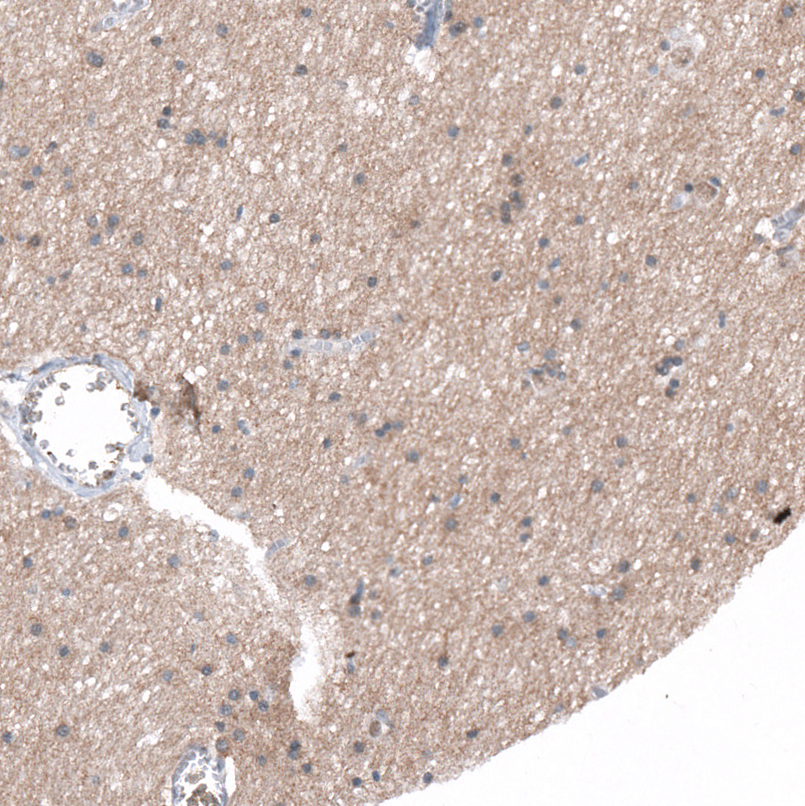

Immunohistochemical staining of human endometrium shows moderate membranous positivity in glandular cells.